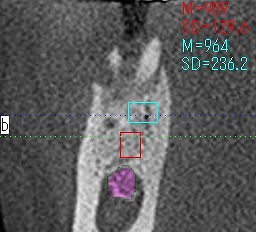

抜歯即時で行うと大穴が開いている状況なので、基準となる骨の位置が分かりにくいです

最初のラウンドドリリングのラウンドバーにて下顎管の距離を測る

CTを取ります

動脈性の出血もなく神経には障害がありませんが、